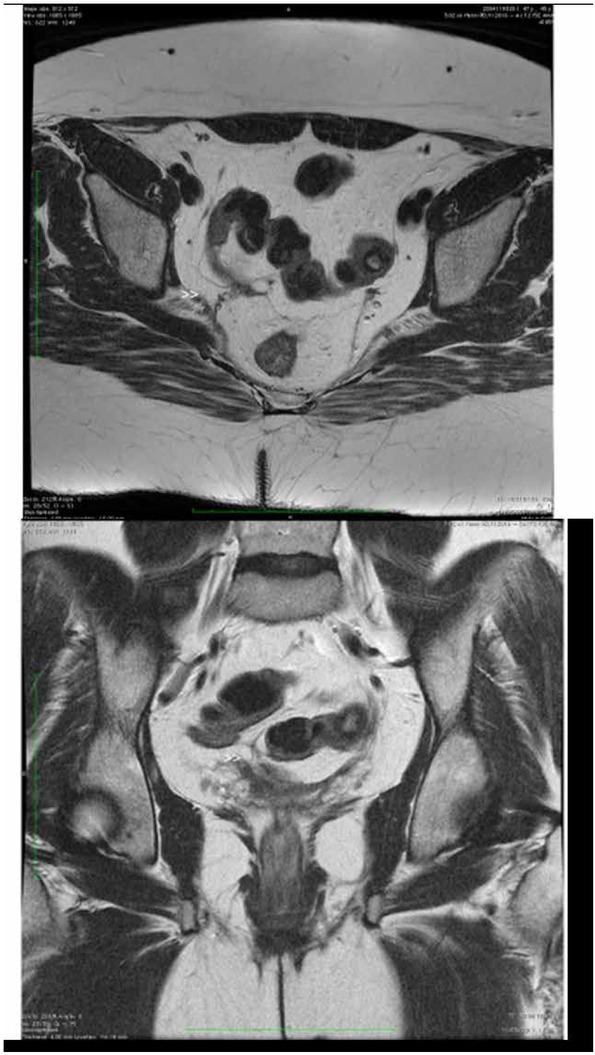

Retroperitoneal fibrosis is a connective disease of the auto-inflammatory/auto-immune type of the retroperitoneum with unknown etiology and pathological mechanism. The manifestations of the pathology can be local or systemic. Amongst the local symptoms, the dull and constant pain in the hips, back or abdomen is the most frequent. We report here a case of a 47-year-old woman, whose pathogenic mechanism could be related to an "IgG4-related disease" disorder as suggested by an increased serum level of this subclass of IgG and the positive immunohistochemistry. The diagnosis is not easy, because this pathology generates masses; adenomegalies with retro peritoneal development, that makes it similar to lymphomas or metastases from ovarian tumors.

腹膜后纤维化是一种发生于腹膜后的、病因及病理机制不明的自身炎症/自身免疫性结缔组织病。其病理表现可为局部性或全身性。在局部症状中,髋部、背部或腹部的钝痛及持续性疼痛最为常见。我们在此报告一例47岁女性病例,其发病机制可能与“IgG4相关性疾病”紊乱有关,依据是该亚类IgG血清水平升高及免疫组化呈阳性。该疾病诊断并不容易,因为这种病理改变会形成肿块;伴有腹膜后发展的淋巴结肿大,这使其类似于淋巴瘤或卵巢肿瘤转移。